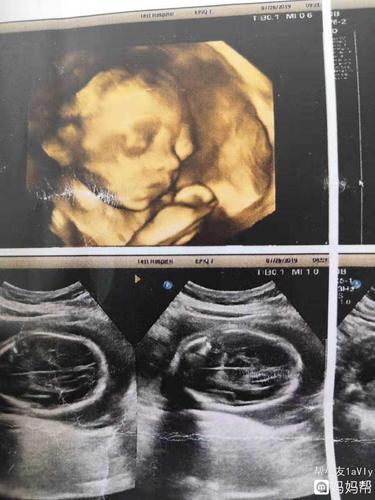

宝宝没有鼻骨的图片,鼻骨缺失长大的儿童

四维检查出宝宝鼻骨未显示,已做羊水穿刺

宝宝没有鼻骨,会不会是畸形

胎儿鼻骨缺失和或发育不良的医生专业指导

没有鼻骨的四维图片

没有鼻骨的宝宝图片